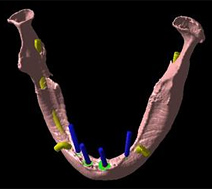

それでは実際にCTで撮影し、CTデータ3D立体構築画像変換検査したものがどう見えるのがご覧下さい。3次元でどこにどのようにインプラントを埋め込んでいけばいいのか、立体的に把握することができます。

下の写真をご覧下さい。

この写真は吉本歯科医院が手術前に行う、3D立体画像構築画面です。

患者さまの下顎の骨、そして神経が見えています。

吉本歯科医院でインプラント治療を行う患者さまの顎の状態は、CT画像だけでなくここまで立体化されたものが手術前には手元にあり、シミュレーションを行ってから実際の手術に入るような流れをとっております。

さて、この写真、黄色くうにょうにょとしているのが神経です。

本来骨の厚みがある患者さまの場合は神経の黄色い部分は骨の中に隠れているため3D立体画像で真上から見た場合かくれて見えません。

この方の場合、骨が神経の出口(オトガイ孔)まで磨り減ったためにこのように写ります。